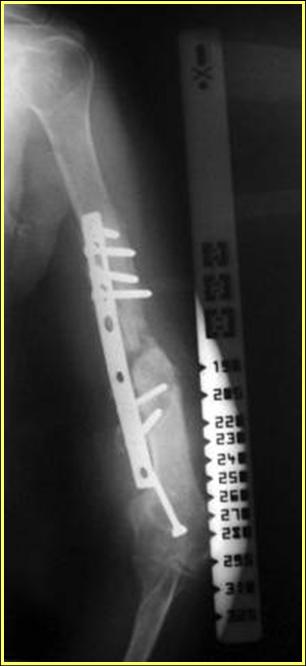

На примере два случая, извиняюсь за качество снимков, снимки и случаи из бывшего союза.

Первая больная с "успехом" была прооперирована 6 раз различными методами открытого и закрытого

остеосинтеза, включая то, что в Кисловодске заезжим австралийским "кудесником" на ложный сустав уложена скорлупа от страусиновых яиц. Последняя операция одиноким локинг плейт в одной из клиник.

Через год по поводу тех же проблем сделали ревизию, оригинальную пластину оставили как есть, только укрепили добавлением еще одной пластины и сделали костную пластику.

Через два месяца увидели признаки консолидации.

Второй случай, также после множественных операций:

пластина, аппарат, серкляж и парез нерва.

Также ревизия, из-за низкого состояния доступ был

сделан через остеотомию локтевого отростка.

Ложный сустав фиксирован двумя локинг плейт с

аутокостной пластикой, также через два месяца увидели признаки консолидации.

Движение в суставе разрешили в две недели.